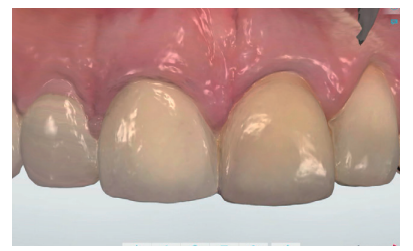

After achieving optimal tissue volume by handling the provisional (Figure 17), an initial scan of the maxilla was performed with the screw-retained provisional crown to obtain the anatomy (Figure 18). Subsequently, a second scan was performed without it, with accurate recording of the gingival contours and the emergence profile achieved (Figure 19), as well as the implant position using the scan body (Figures 20 and 21). For proper recording of the emergence profile, the provisional crown was scanned outside the mouth (Figures 22 and 23); thus avoiding having to perform the classic technique of an individualised transfer17. These records were sent to the prosthetic laboratory, which designed a post-machined sintered metal structure (Figure 24). Once the framework test had been satisfactorily carried out (Figure 25), the colour of the restoration (A2 VITA guide) was taken using a polarised light filter (Figure 26). These records were sent back to the prosthetic laboratory for completion of the implant-retained crown on the printed models (Figures 27 and 28). Prior to the placement of the definitive crown, the emergence profile of the provisional crown was compared with the final one, and the similarity observed between them (Figure 29); thus managing to preserve the profiles maintained from the day treatment was started.

After the 6-month review, excellent stability of all periimplant tissues was verified, with correct volume at the vestibular level, as well as the maintenance of optimal aesthetics and functionality (Figure 30).